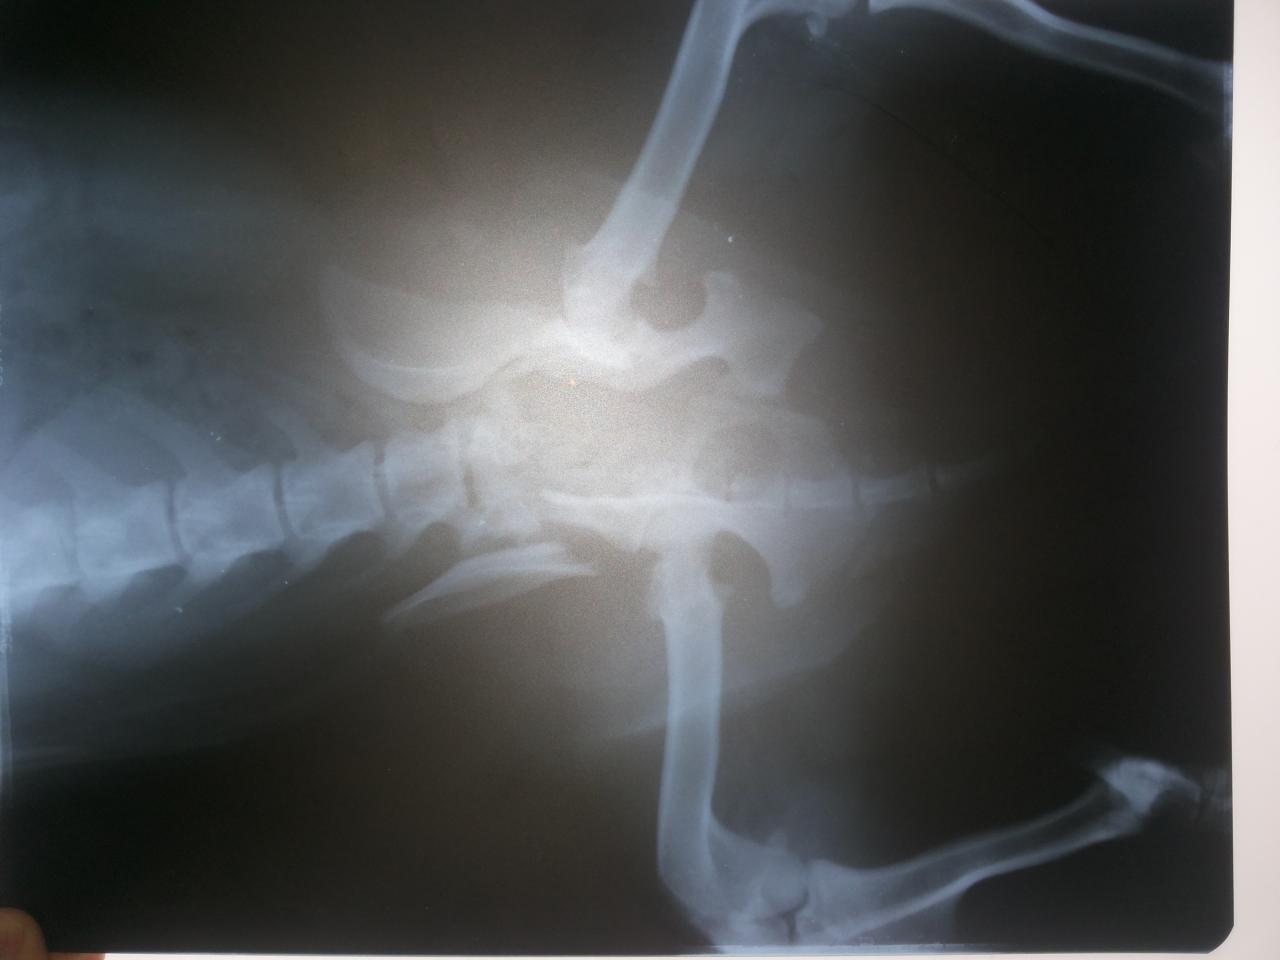

У меня за эти годы было несколько подопечных с переломами и травмами таза, две трети из них обошлись без операции вообще, таз часто срастается сам, если животное находится в клетке в состоянии покоя.